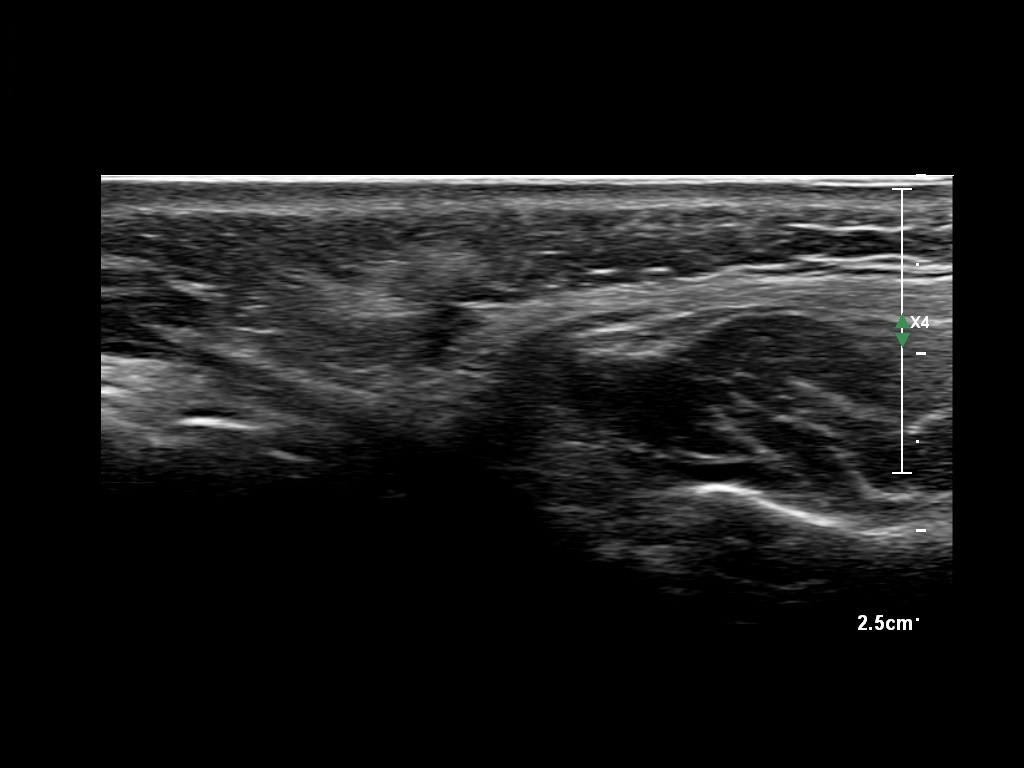

Draw in the second image below where the fillers are located. To check if your answer is correct, swipe the first image to the right.